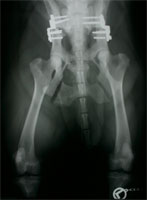

In Studien, die sich über einen Zeitraum von 8 Jahren erstreckten, zeigten 76 % der DBO-Operierten noch ein exzellentes Ergebnis ohne Coxarthrose mit uneingeschränkter Beweglichkeit und völliger Schmerzfreiheit (Abb. 16). Bei dem Rest der Patienten zeigten sich röntgenologisch leichte Arthroseerscheinungen, die klinisch jedoch zu keiner Einschränkung der Bewegung führten und in der Regel auch keine Gabe von Schmerzmitteln erforderten.

DBO arthrosefreies Hüftgelenk nach 8 Jahren

Abbildung 16: Arthrosefreies Hüftgelenk, welches acht Jahre zuvor mit einer Dreifachen Beckenosteotomie stabilisiert wurde.

DBO bilateral Ausheilungsergebnis

Abbildung 17: Ausheilungsergebnis einer bilateralen Dreifachen Beckenosteotomie. Die bisweilen ausbleibende Fusion des Os ischium ist klinisch bedeutungslos.

Fazit

Die Dreifache Beckenosteotomie (DBO) beseitigt nicht nur die Lockerheit des dysplastischen Hüftgelenkes sondern führt zu einem festen und tiefen Sitz des Caput ossis femoris im Acetabulum. Die tragende und belastete Gelenkfläche wird durch die Umstellung verdreifacht bis vervierfacht. Dies führt den Stress auf den Gelenkknorpel in physiologische Dimensionen zurück. Im Idealfall sind im weiteren Verlauf keinerlei röntgenologische Anzeichen einer Coxarthrose zu verzeichnen (Abb. 17). Treten sie bei operierten Patienten mit schwersten HD Graden später dennoch auf, so sind sie von der Form her milde und von keiner Lahmheitssymptomatik begleitet. 92 % der Patienten sind nach spätestens 7 Monaten völlig lahmheitsfrei. Langzeitstudien beweisen, dass die Hunde im Laufe ihres Lebens klinisch fast immer beschwerdefrei sind und selbst im Alter weder antiphlogistische Medikamente noch neuerlicher chirurgischer Interventionen bedürfen. Es wäre wünschenswert, wenn die Tierbesitzer dysplastischer Junghunde mehr über die Chancen und Möglichkeiten informiert würden, die die Dreifache Beckenosteotomie eröffnet. Sie ist bei korrekter Indikationsstellung sowie Erfahrung der Operateure der Goldstandard in der Therapie der juvenilen Hüftgelenksdysplasie und ein Jahrzehnte lang international erprobtes und bewährtes Verfahren.